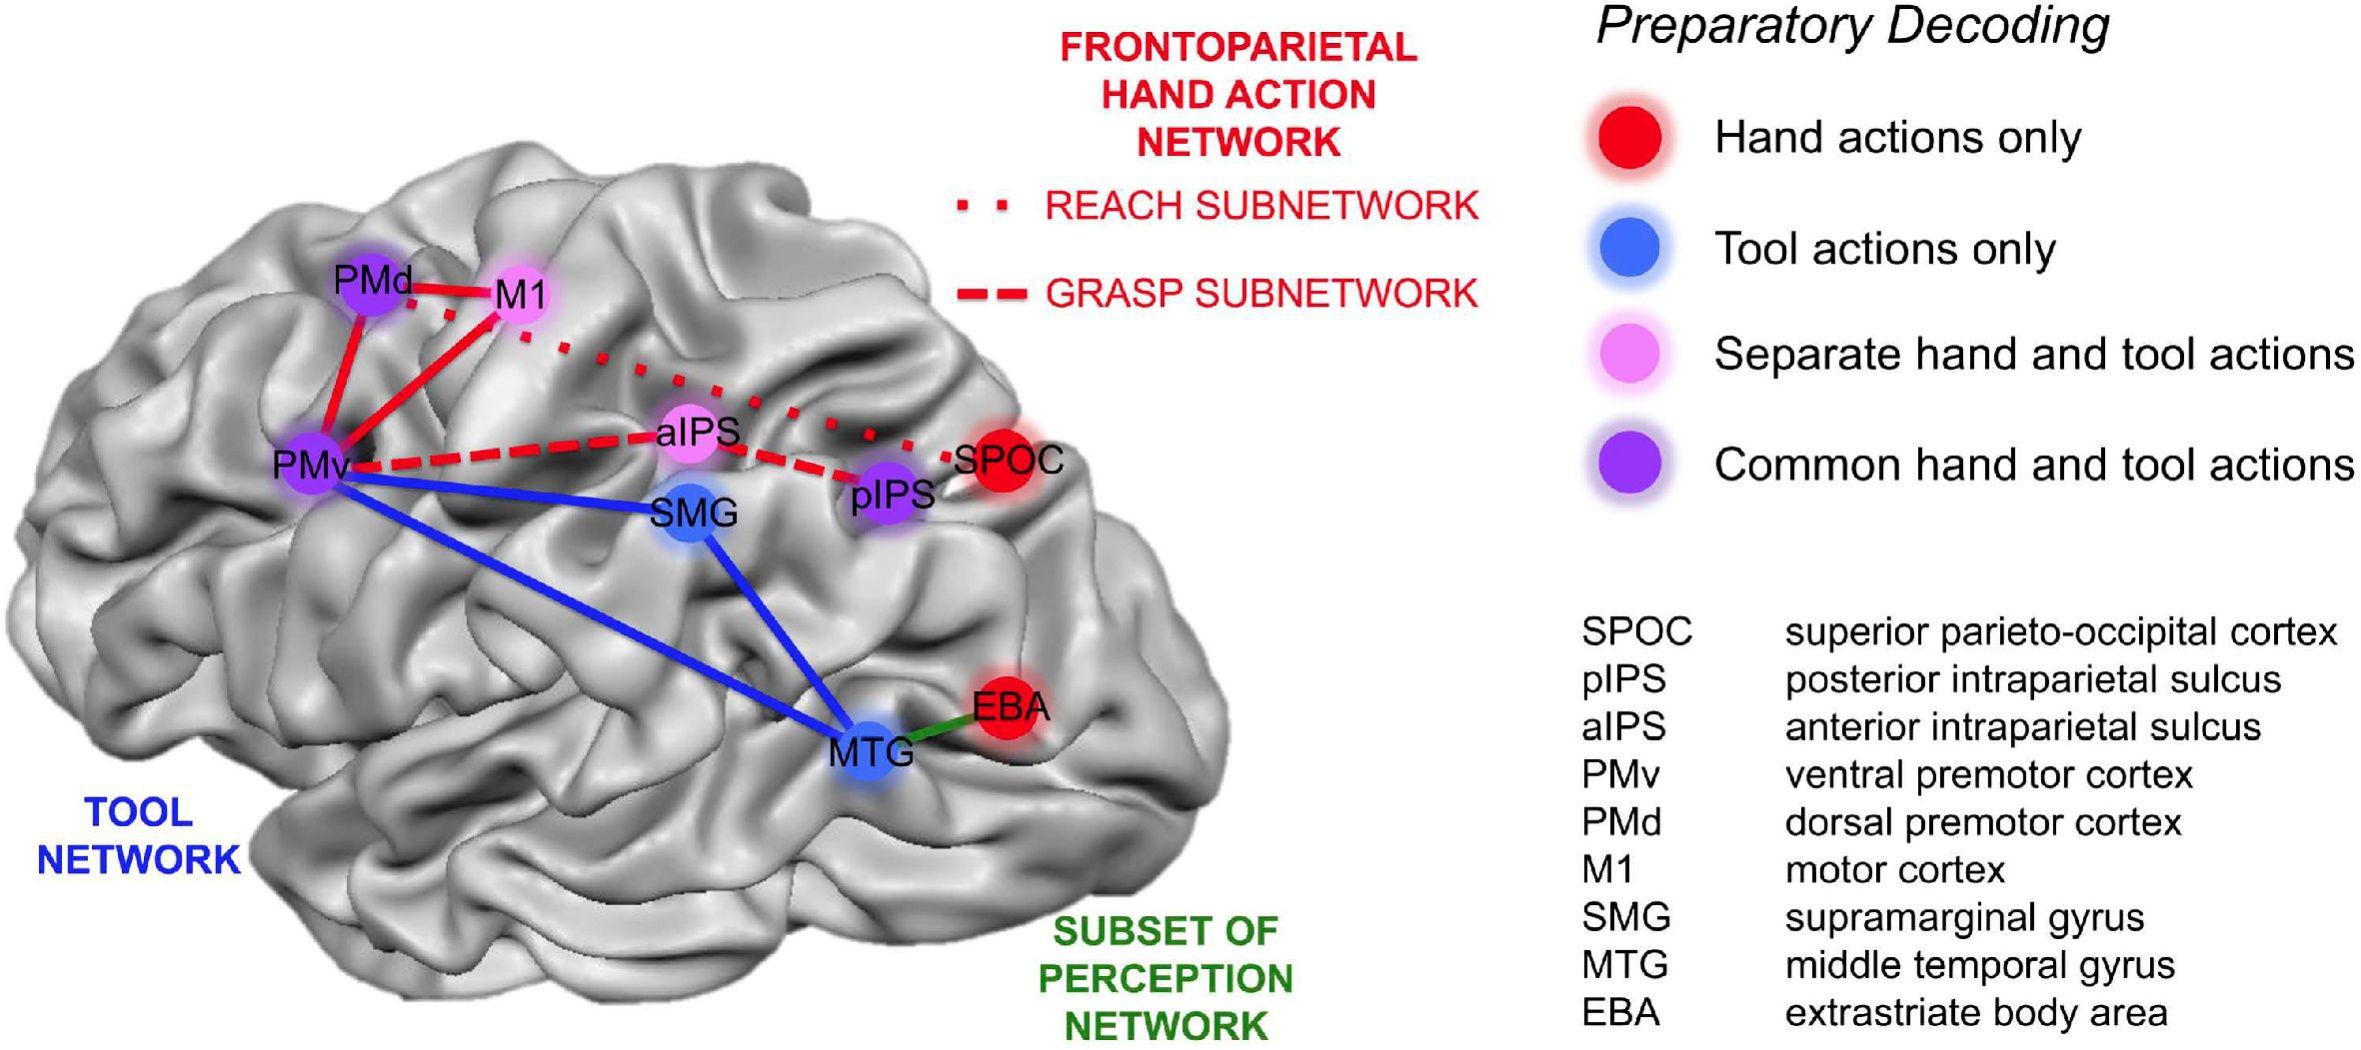

Супрамаргинальная извилина: Функции и Исследования

Раздел: Моменты озарения